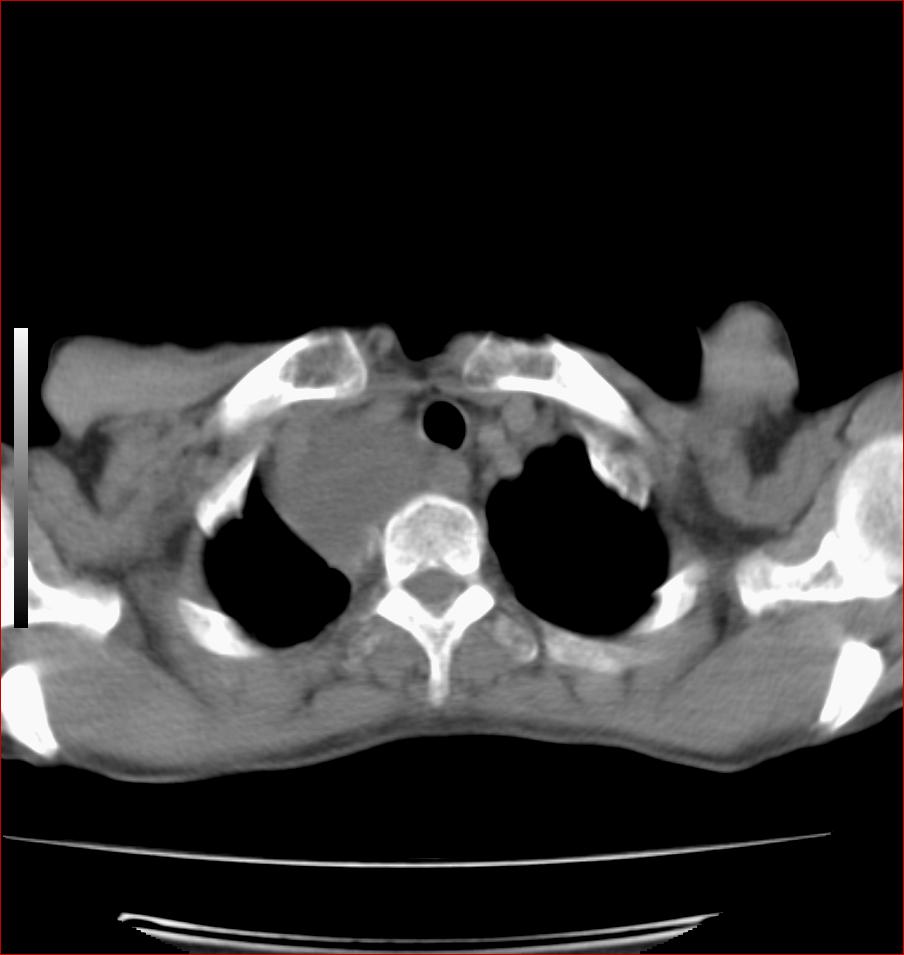

标题: CT17110:F56Y,纵隔囊肿;胸腺?淋巴?请各位老师看看 [打印本页]

标题: CT17110:F56Y,纵隔囊肿;胸腺?淋巴?请各位老师看看

女性患者 56 咽痛伴声嘶10+天入院。

气管囊肿

先考虑---------支气管囊肿

右上纵隔囊性占位性病变;考虑支气管囊肿可能。

见相互挤压征,考虑气管囊肿,建议ct增强扫描